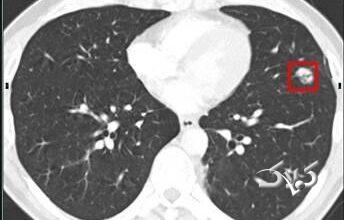

یک آزمایش واجب برای افراد سیگاری بالای ۵۰ سال

دانشمندان میگویند با اینکه هنوز سرطان ریه کشندهترین سرطان است، اما پیشرفتهای عمده در غربالگری، جراحی و درمان شخصیسازیشده به…